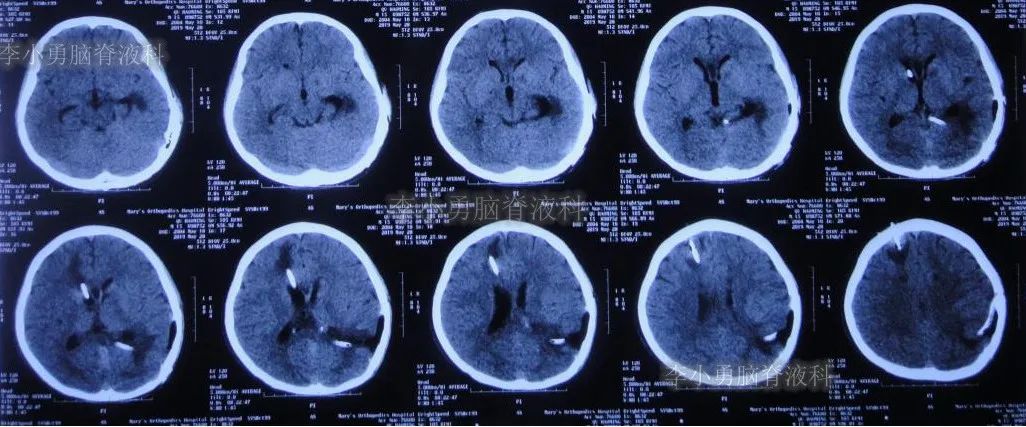

双侧脑室外引流5天后即2019年3月31日,脑脊液颜色由血性明显变淡,意识转清,肢体活动良好,给予复查头颅CT(图-3):脑室不大,残留少许积血。

图-3:2019年3月31日头颅CT:残留少许积血

双侧脑室外引流6天即2019年4月1日,给予常规拔除双侧脑室外引流管。但当晚再次出现剧烈头痛、烦躁及恶心,复查头颅CT(片子遗失)示脑室内再次出血,给予“对症处理”。

次日即2019年4月2日给予行腰椎穿刺术,引流出血性脑脊液;但腰椎穿刺术刚结束突然晕厥,再次复查头颅CT(图-4):脑室内出血量较前明显增多,四脑室及中央导水管铸形。

图-4:2019年4月2日头颅CT:脑室内积血明显增多